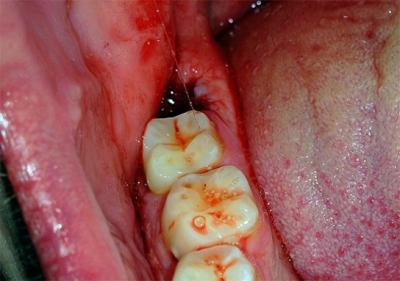

По окончании процедуры не рекомендуется приступать к еде и напиткам ещё в течение 2–3 часов. Это время необходимо для того, чтобы в лунке сформировался плотный кровяной сгусток.

Именно он способствует остановке кровотечения и будет являться естественной преградой, препятствующей проникновению остатков пищи и инфекции в рану, что, несомненно, привнесёт осложнения в процесс её заживления.

Марлевый тампон, которой стоматолог поместил на рану, следует удалить не раньше, чем через 20–30 минут, а в случае наличия некоторых проблем со здоровьем пациента (высокое кровяное давление, плохая свёртываемость крови) — не ранее 40–60 минут.

Эта мера также обусловлена созданием необходимых условий для быстрого заживления раны: тампон, зажимая лунку, останавливает капиллярное кровотечение и способствует формированию кровяного сгустка вместо зуба.